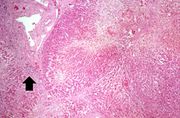

| 14:53, 20 August 2013 | IPLab5Hemochromatosis3.jpg (file) | 23 KB | This is a low-power micrograph of liver from this patient. Note the nodularity of the tissue (arrows). | 1 | |